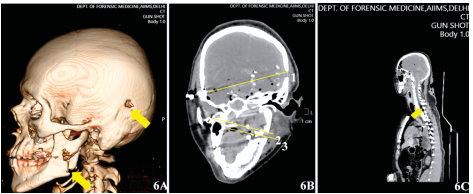

Description: 6A: Entry wound on occipital region and mandible. 6B: Foreign bodies at right temporal region due to

entry wound (1) and under right zygomatic process from the entry wound (2). 6C: Pneumorrhachis.